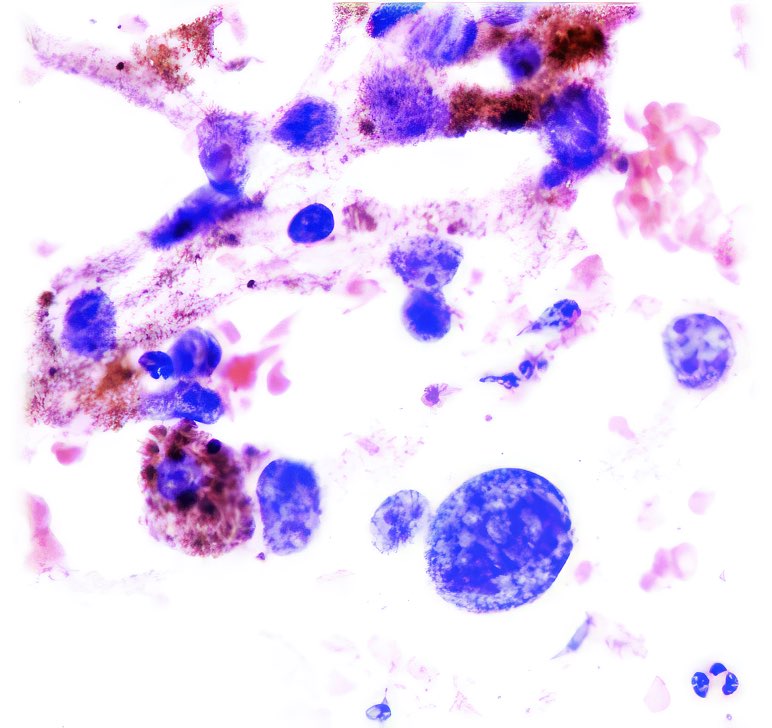

Abb. 1 - 4: Fremdkörper im Urinsediment, Pap, Abb. 2 u 4 bei polarisiertem

Licht;

ursprüngliche Vergrößerung 400x

Abb. 1 und 2 zeigen in einem Haufen angeordnete Pflanzenzellen, Abb. 3 und 4 einzelne dieser Zellen bei etwas höherer Vergrößerung. Nur die relativ dicken kapselartigen Zellmembranen sind sichtbar, keine anderen Zellstrukturen. Im polarisierten Licht sind die Zellmembranen deutlich doppelbrechend (Abb. 2 und 4).